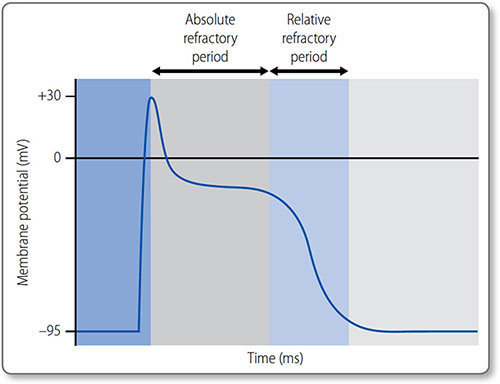

Refractory periods

The absolute refractory period is the time during phases 1 and 2 in which another action potential cannot be initiated. It is due to inactivation of fast Na+ channels, which are not reactivated until phase 3. The relative refractory period is the time during their reactivation, when depolarization can occur but depends on the magnitude of the stimulus and the number of reactivated channels (Figure 1.23).

Figure 1.23: The absolute and relative refractory periods of an action potential in a cardiomyocyte.